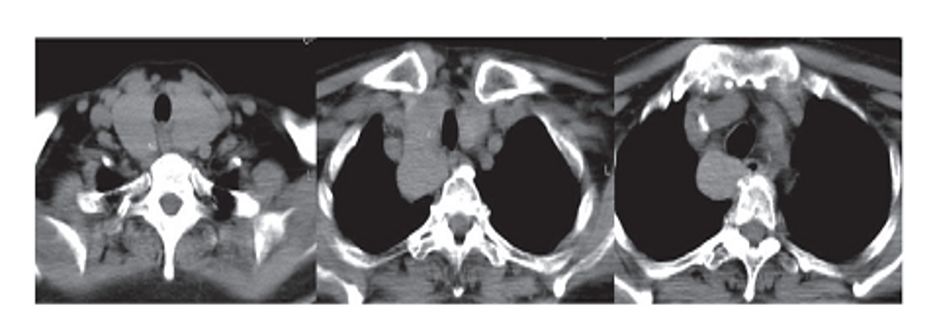

图1胸腺瘤A;图2胸腺瘤AB;图3胸腺瘤B;图4胸腺癌

1.胸腺瘤

胸腺瘤是前纵隔肿瘤最常见的原发性肿瘤,约占50%。

部位:前纵隔中部偏上。

形状:圆形或分叶状实性肿块。

密度:多均匀,可有坏死、钙化。

边缘:良性清楚,病变周围脂肪间隙存在;恶性不清,病变周围脂肪间隙,消失,胸腔及心包可有积液。

增强扫描:实性部分中等强化,坏死区不强化。

组织学分型:A型和AB型为良性肿瘤,B1型为低度恶性,B2型为中度恶性,B3型与胸腺癌均为高度恶性,侵袭性强。